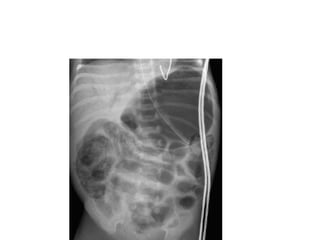

imaging

• Multiple gas filled loops of intestine

• Pneumatosis intestinalisc: pathognomonic for

NEC

• a collection of cystic or linear lucencies in the

bowel wall,

• Frequency may reach 19-98%but may be

absent in upto 14% of cases of NEC

imaging • Multiple gasfilled loops of intestine • Pneumatosis intestinalisc: pathognomonic for NEC • a collection of cystic or linear lucencies in the bowel wall, • Frequency may reach 19-98%but may be absent in upto 14% of cases of NEC

• 25.

• Portal venousgas: linear branching radiolucencies overlying the liver and often extending to its periphery • incidence of 10% to 30%.poor prognosis • Pneumoperitoneum: in 12-30% of patients • Best seen on lateral decubitus film • Football sign, double wall sign, • Only 63% of patients with perforation show the xray sign